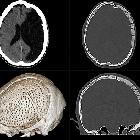

Computertomographie

sagittal im Hirnfenster und Knochenfenster sowie als Volumenrendering bei Zustand nach Erweiterungsplastik am Foramen magnum mit Resektion des hinteren Atlasbogens bei Chiari-1 Malformation.